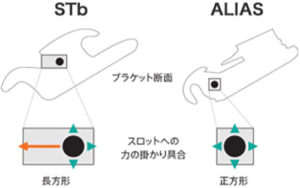

従来の装置はワイヤーを通す溝が長方形でしたが、アリアスは世界初の正方形になっています。

そうすることで力のかかり具合をコントロールしやすく、従来の長方形の溝に比べて確実に早く歯を動かせ、仕上がりもより美しくすることが可能になりました。